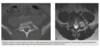

Q

39 yo man fall

Axial T2 fat sat MR - bone contusions in medial patella and lateral femoral condyles (Arrows) with associated tear of medial retinaculum (Arrowhead)

Diagnosis: Acute patellar dislocation relocation

Occurs with internal rotation of femur on fixed and externally rotated femoral condyle - bone contusions on both.

Due to direct impaction, associated with ACL tears.

Radiographs = Lipohaemarthrosis or chip fracture adjacent to donor site of medial facet of patella.

MR findings = Disruption or sprain of the medial retinaculum, lateral patellar tilt or subluxation, lateral femoral condylar and medial patellar osseous contusions. Osteochondral injury to medial patella or lateral femur.